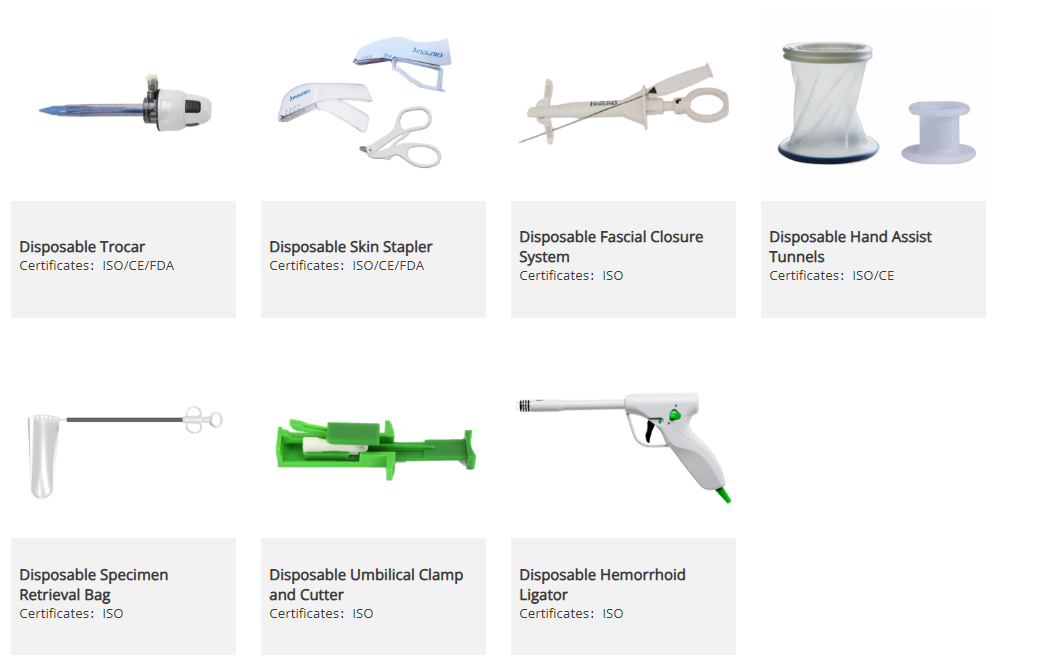

Basic Disposable

Essential single-use medical items designed for routine clinical use, such as syringes, catheters, infusion sets, masks, etc. These disposables ensure hygiene, prevent cross-contamination, and support safe and efficient patient care across healthcare settings.

Endoscopic Stapler

An endoscopic stapler is a surgical device used in minimally invasive procedures to cut and staple tissue simultaneously. It enables precise tissue closure and secure anastomosis, supporting efficient and safe surgical interventions across various laparoscopic procedures.

Polymer Ligating Clips

Polymer ligating clips are sterile, single-use devices designed to securely ligate blood vessels and tissue structures during surgical procedures. Made from high-strength polymer materials, they provide reliable closure, easy application, and secure fixation in both open and minimally invasive surgeries.

Open Staplers

Open staplers are surgical devices used in conventional (open) procedures to cut, close, or connect tissue efficiently. They provide secure and consistent tissue stapling, helping surgeons achieve reliable closure and improved efficiency during a wide range of surgical interventions.

Accessories